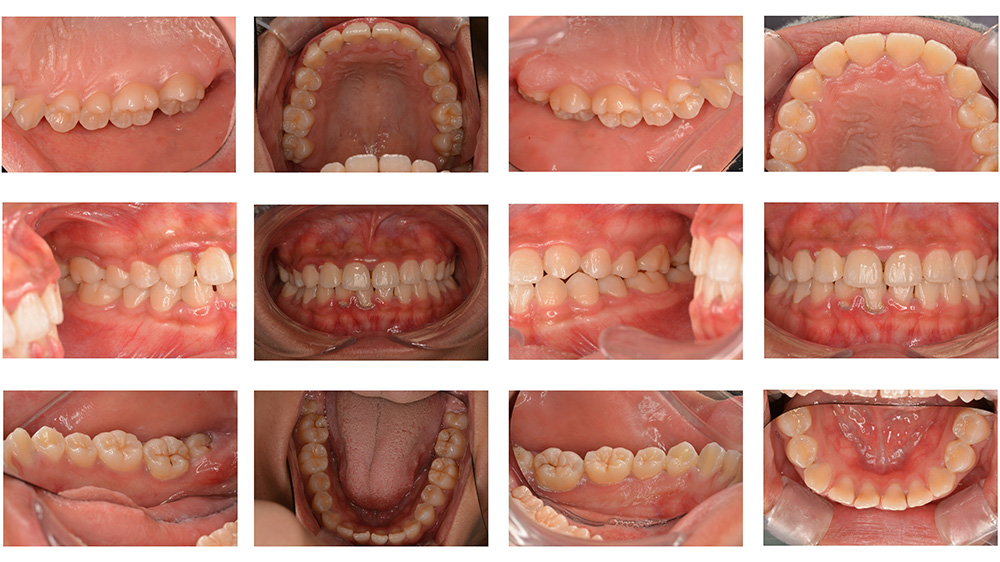

術前

術後

世代・性別

10歳女性

主訴

前歯が出ているのを治したい

治療内容

筋機能矯正治療(治療途中)

治療期間

4ヶ月

治療費

27万円(税別)

治療のリスク

歯の移動に伴う痛み